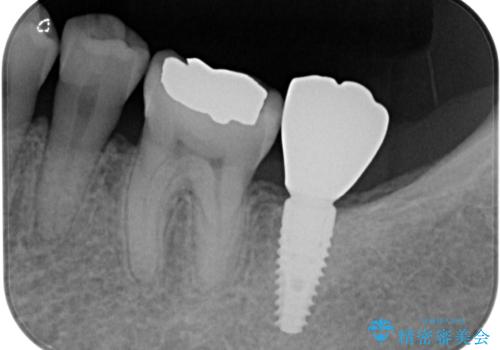

- 上下前歯の反対咬合と左下奥歯の痛みを気にして来院された患者様です。

歯並びや口元の印象、奥歯の咬み合わせから、非抜歯にて矯正治療を行うこととしました。

また、左下の奥歯は親知らずの影響で手前の歯の歯根までむし歯になってしまったため、親知らずとともに抜歯をし、インプラントによる補綴治療を行うこととしました。

インプラント埋入による仮歯の装着や、前歯の反対咬合の改善は比較的スムーズに達成されましたが、舌突出癖などの影響による、歯列全体のスペースを閉じることが難航し、期間がかかってしまいました。